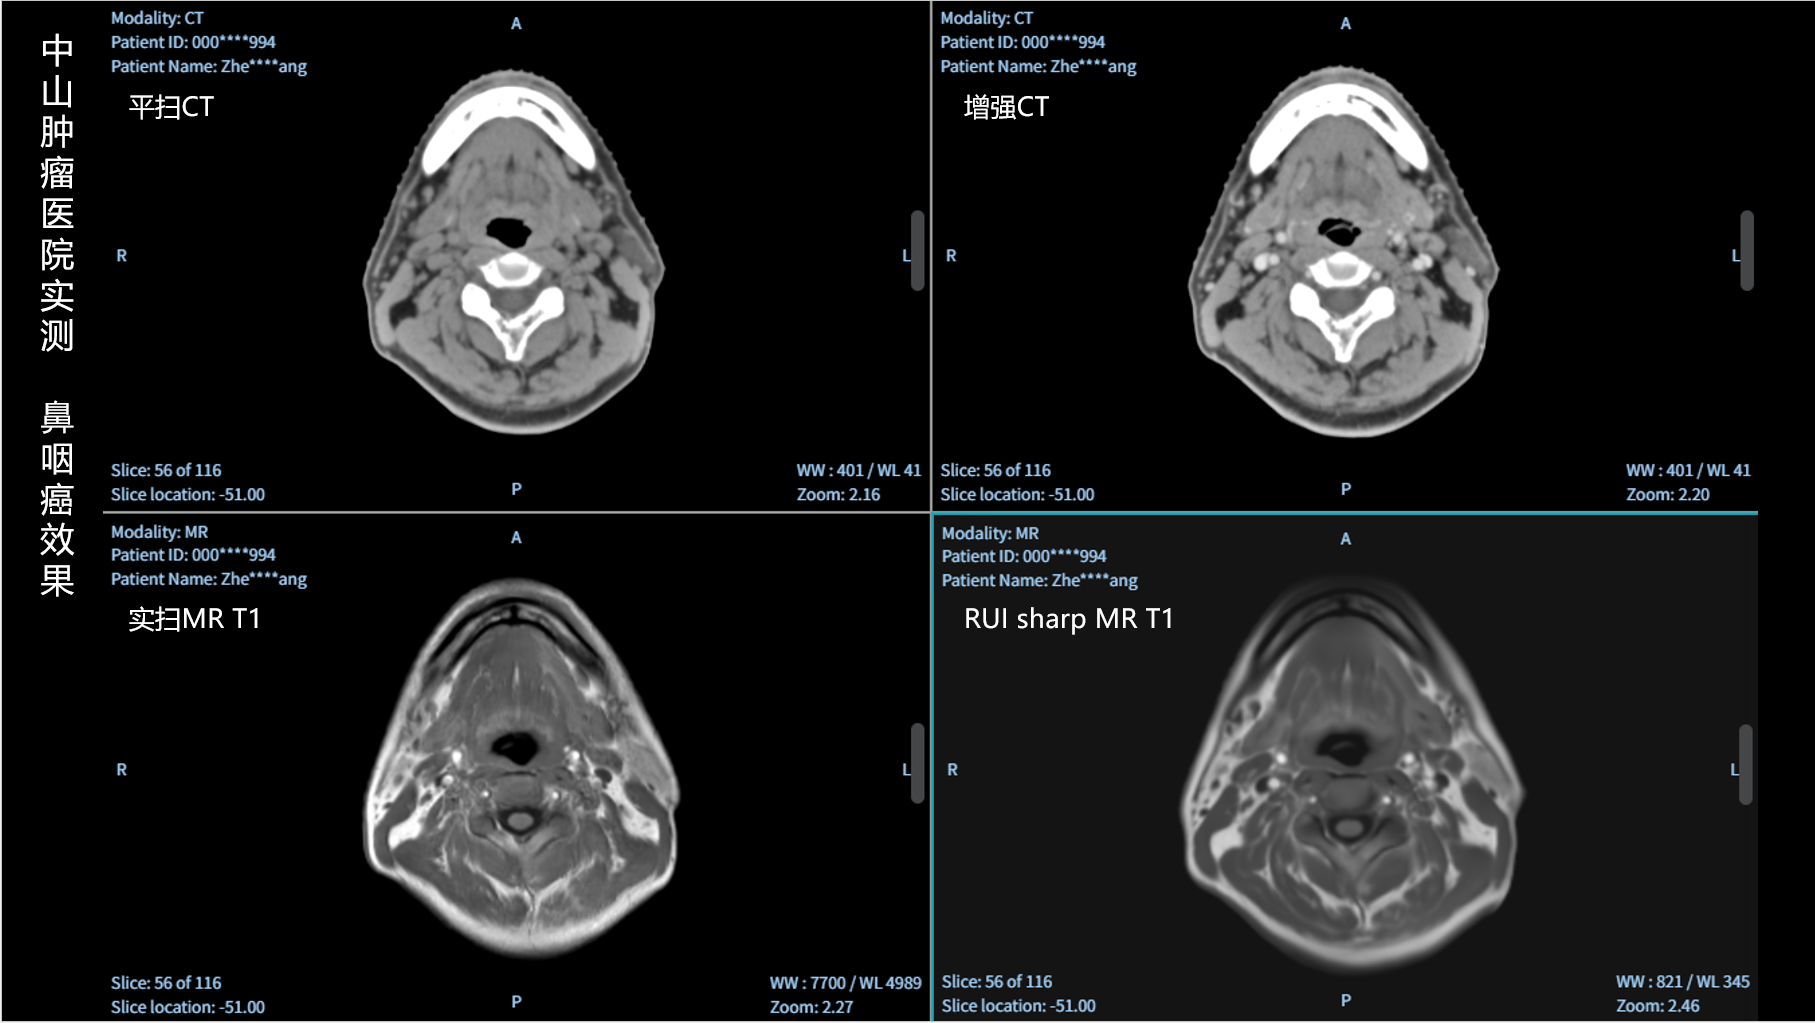

RUI sharp H(锐影)可在不依赖MRI的前提下,显著提升头部CT图像的软组织分辨率,为临床提供更高质量的辅助信息,尤其适用于MRI资源受限或较难配准的头颈部放疗感兴趣区勾画场景。

可大幅提高头部CT影像软组织分辨率,使肿瘤和周边器官显示更清晰,为放疗靶区勾画提供参考。

无需图像配准,CT和锐影图像同源,可匹配、叠加、"淡入淡出"显示。

实测效果